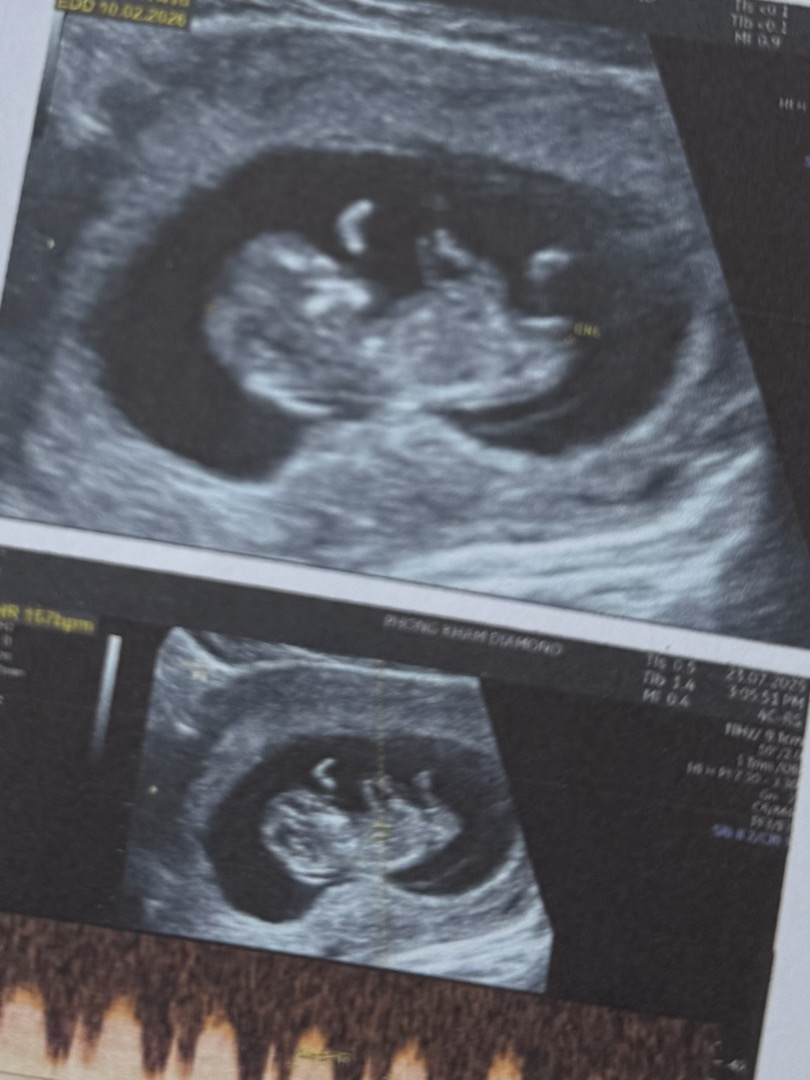

딸인가용?아들인가용? 봐주세요ㅠㅠㅠ

베트남에 여행왓는데 애기 잘잇는지 궁금해서 병원갓어용! 보기에는 아들같나요?딸같나요?ㅠㅠㅠ 선생님께서는아는눈치인거같은데 안 가르쳐주네오ㅠㅠ